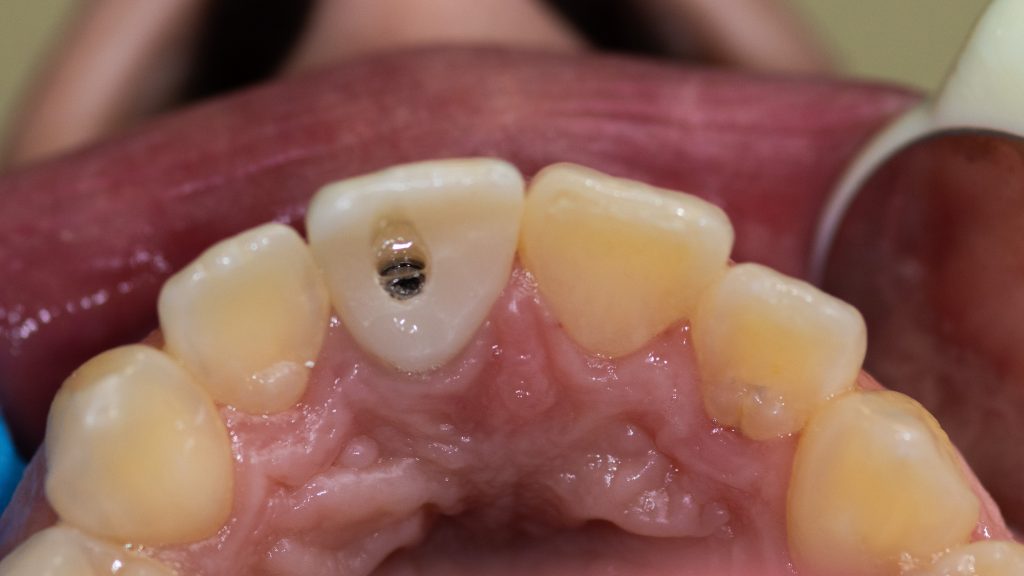

Final Restoration